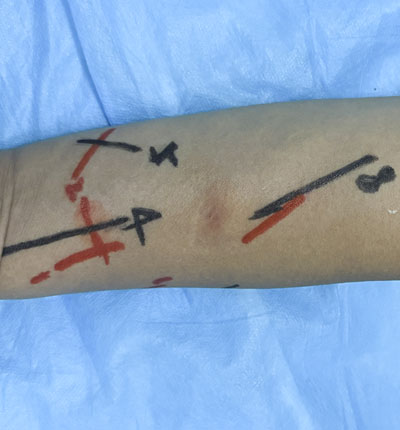

术前定位